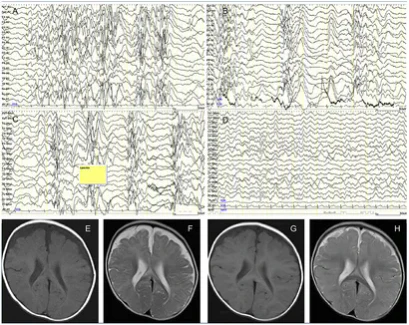

Электроэнцефалография: характерной находкой для диагностики инфантильных спазмов является паттерн гипсаритмии. Он характеризуется высоковольтными, хаотичными медленными волнами и пиками во всех корковых областях. Пики могут возникать генерализованно, но они никогда не бывают ритмичными или организованными. Другие межприступные паттерны у пациентов с СВ включают фокальные или мультифокальные пики и острые волны, диффузное или фокальное замедление, пароксизмальные вспышки медленной или быстрой активности, а также паттерны «медленный пик — волна»[6].

Компьютерная томография головного мозга: структурные аномалии головного мозга, такие как гидроцефалия, гидранэнцефалия, шизэнцефалия и агенезия мозолистого тела, могут быть выявлены с помощью компьютерной томографии. Кроме того, церебральные кальцификаты можно наблюдать у пациентов с туберозным склерозом или внутриутробными инфекциями[5].

Магнитно-резонансная томография головного мозга: используется для выявления очагов корковой дисплазии, нарушений нейрональной миграции или миелинизации[5].